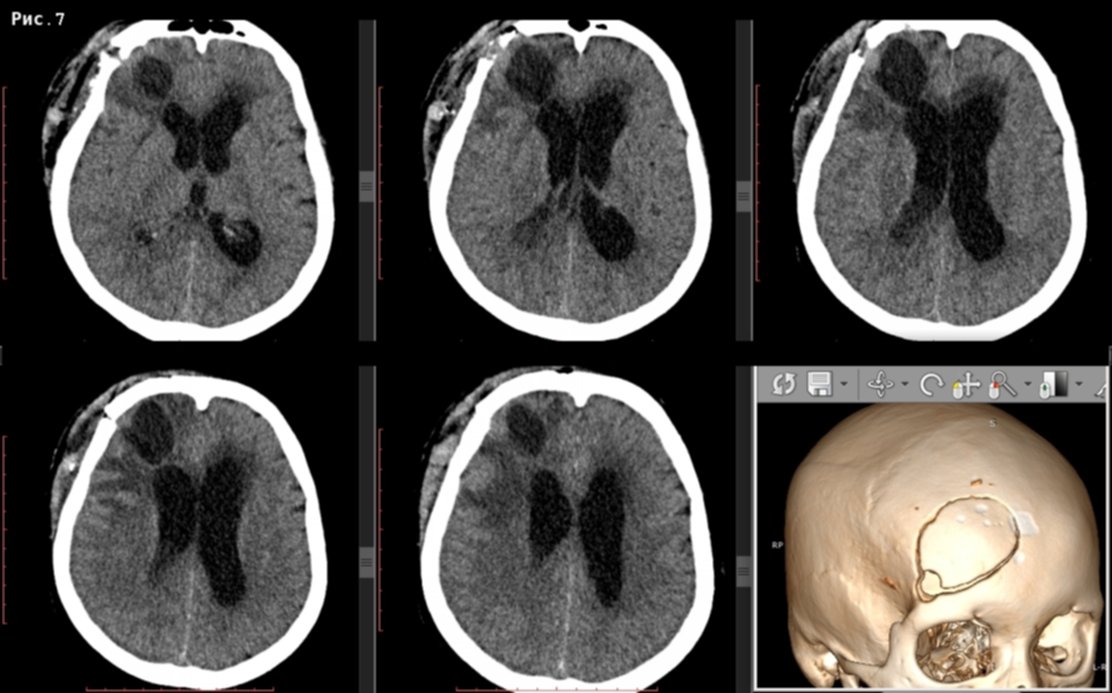

Кт видит мозг

Кт видит мозг 82 фото